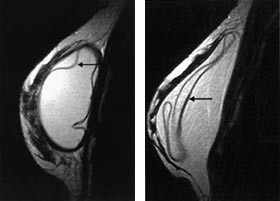

T2-vektede bilder i aksial- og sagittalplan gir god informasjon om silikonskallets integritet og differensierer godt mellom silikongel (høyt signal) og brystkjertelvev (lavt signal) (fig 5a ). Imidlertid vil subkutant fettvev og silikongel ofte ha relativt lik signalintensitet. Finner man tegn til implantatruptur på T2-vektede bilder, bør man derfor supplere med bildesekvenser som skiller godt mellom fettvev og silikon for å kunne påvise mulige silikonlokulamenter i fettvevet. Et eksempel på en slik sekvens er en ”inversion recovery” med kort T1 (STIR)-sekvens (fig 5b).

En intakt enkeltlumen silikonprotese er oftest oval med jevn overflate. Silikonskallet er signalfattig på alle typer bildesekvenser. Skallet er som regel vanskelig å skille fra den fibrøse bindevevskapselen som dannes rundt implantatet. Radiære innfoldinger av proteseskallet sees hyppig og må ikke forveksles med ruptur (fig 6). Innfoldingene kan være markerte, men kan alltid følges ut til protesens overflate. Reaktiv væske rundt implantatet sees ofte og er ikke et tegn på ruptur. Er væskemengden uttalt, kan et enkeltlumen silikonimplantat feiltolkes som et dobbeltlumenimplantat med et ytre saltvannslumen. I dobbeltlumenimplantater (fig 7a) vil ofte det indre skallet som skiller de to lumen vise uttalte innfoldinger, uten at dette er tegn på ruptur. Noen ganger kan implantatet herniere ut gjennom små defekter i den fibrøse kapselen som omgir protesen (fig 7b). Dette kan gi palpable resistenser og oppfattes klinisk som en brysttumor.